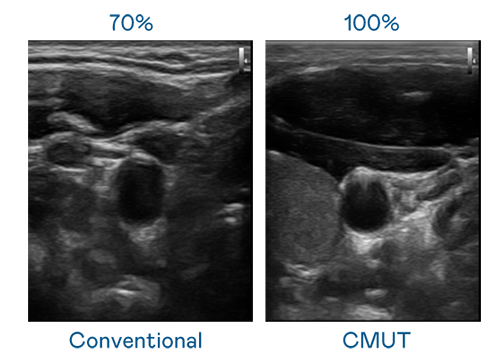

CMUT 技术是一种用电容式微机电元件来产生超音波讯号的技术。与传统 PZT 压电式技术相比,CMUT 频宽增加 30%,更宽频的超音波讯号让影像解析度大幅提升,是实现高影像品质医疗超音波扫描、促进精准医疗发展的关键技术。

大频宽带来超清晰影像

超音波影像的解析度高低,首先取决于探头能发出的讯号频宽。Top1体育 CMUT 可提供高清晰的超音波讯号,提供高频宽、高灵敏度、影像纹理细节更高的超音波影像,协助医护人员缩短影像判读时间及利用精准的医疗影像进行诊断。